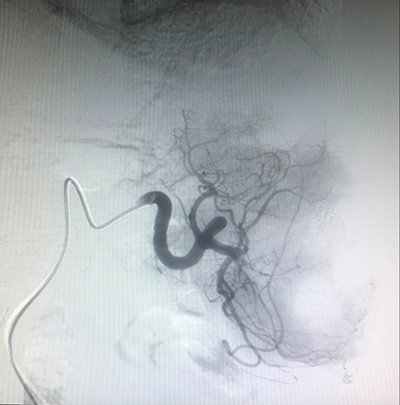

![]() | ![]() |

| (脑肿瘤的介入治疗) | (子宫肌瘤的介入治疗) |